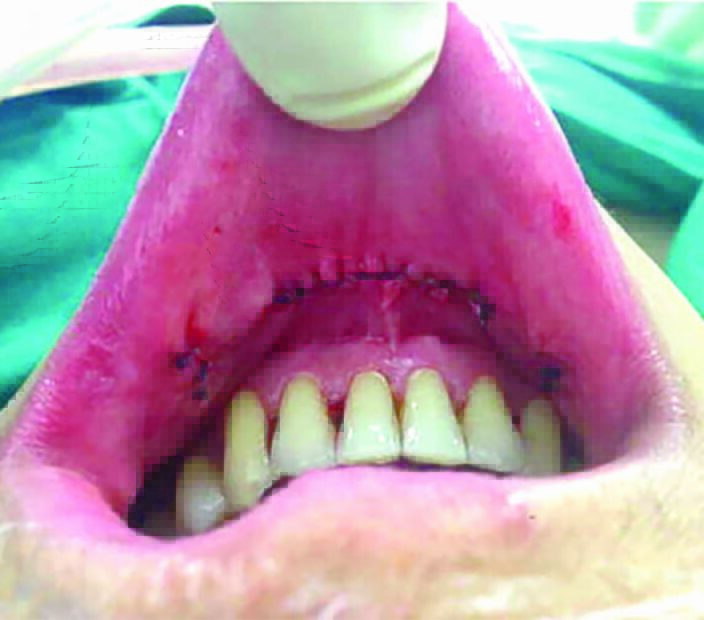

ทั้งนี้ การผ่าตัดต่อมไทรอยด์ผ่านทางช่องปาก เป็นเทคนิคการผ่าตัดวิธีล่าสุดที่ได้รับการพัฒนาจนเป็นที่ยอมรับและได้รับความนิยมแพร่หลายไปทั่วโลก โดยจะใช้เทคโนโลยีกล้องขนาดเล็กที่มีความละเอียดสูงช่วยในการผ่าตัด ทำให้แผลผ่าตัดมีขนาดเล็ก โดยแผลจะอยู่บริเวณด้านในของริมฝีปากล่าง ตรงกลางขนาด 1.5 เซนติเมตร และด้านข้างอีก 2 จุด ข้อดีคือไม่ก่อให้เกิดรอยแผลเป็นหลังการผ่าตัด ลดระยะเวลาการผ่าตัดและทำให้คนไข้เจ็บปวดน้อยและฟื้นตัวเร็ว